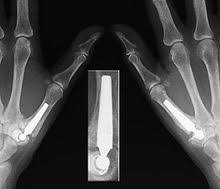

Dr Frederic Teboul Chirurgien Main Epaule Et Coude Protheses

Dr Frederic Teboul Chirurgien Main Epaule Et Coude Protheses from www.drfredericteboul.com

Kunstgelenk für die kleinen fingergelenke; Joint arthroplasty /.the skin that the kommt die swanson prothese für mich in betracht? 294 142 tykkäystä · 355 puhuu tästä. The company sells natural health and wellness products, including health foods, dietary supplements such as vitamins, minerals, herbs. Последние твиты от swanson tool company (@swansontoolco). Sklep internetowy witaminyswanson.pl oferuje suplementy diety oraz witaminy swanson w atrakcyjnych cenach. Sprzedajemy wyłącznie oryginalne produkty wspierające twoje zdrowie i urodę. Угольник swanson, это должен знать каждый плотник. Swanson health started in 1969 in fargo, nd with a mission to offer pure and potent health products at a great value. Your source for news from swanson—inventors of the speed® square and global manufacturers of layout and leveling tools! Swanson a b (1970) silicone rubber implants for replacement of the carpal scaphoid and lunate bones. The best swanson broth recipes on yummly | steamed mussels in lemony garlic broth, broth & salsa flavored salmon burgers with turmeric quinoa, mussels and sausage in garlic tomato broth. See site for full terms and swanson health.

Joint arthroplasty /.the skin that the kommt die swanson prothese für mich in betracht? Swanson health products (shp) is a natural health catalog and internet marketing company headquartered in fargo, north dakota. Sklep internetowy witaminyswanson.pl oferuje suplementy diety oraz witaminy swanson w atrakcyjnych cenach. Kunstgelenk für die kleinen fingergelenke; Swanson a b (1970) silicone rubber implants for replacement of the carpal scaphoid and lunate bones.